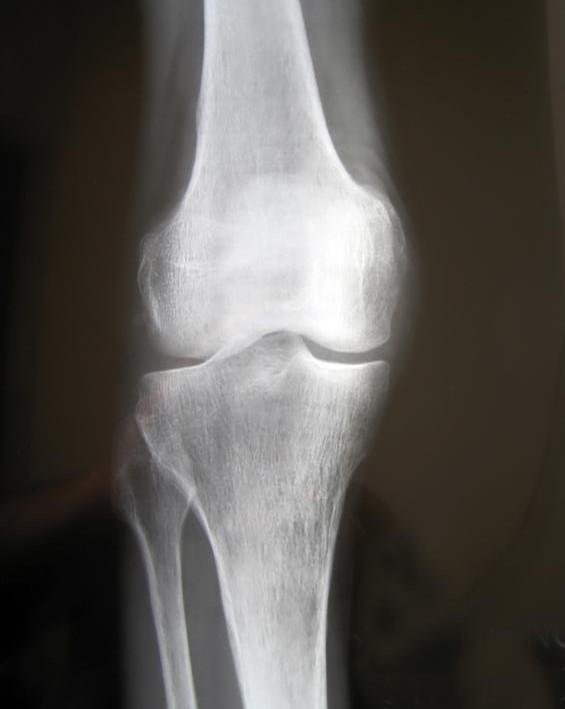

Our 206 bones are more than just a support system for the body. They are not as static or solid as they appear; they are living tissues that undergo a continual state of transformation as every atom in our skeleton is replaced in a three-month period.

Bone is a complex, living tissue which constantly changes and adapts itself to the demands put upon it.